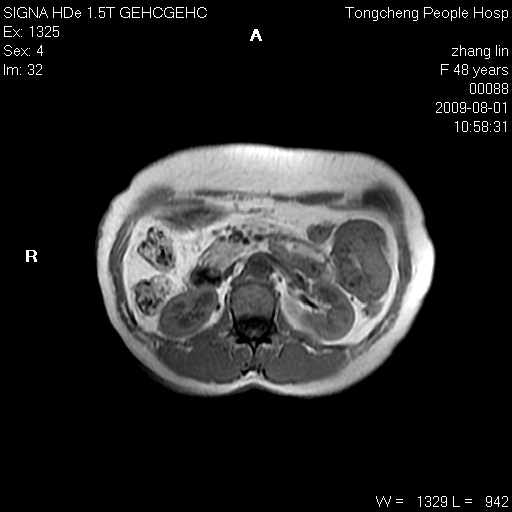

女,48岁。健康体检,彩超发现右肾占位性病变。平素健康。

临床诊断:右肾占位性病变,性质待定(囊肿?肿瘤?)。

上中腹部mr平扫+增强扫描,图像如下:

右肾上极见一类圆形病灶,t1wi呈等信号t2wi呈等高混杂信号,三期增强无强化,边界清---考虑囊肿出血。